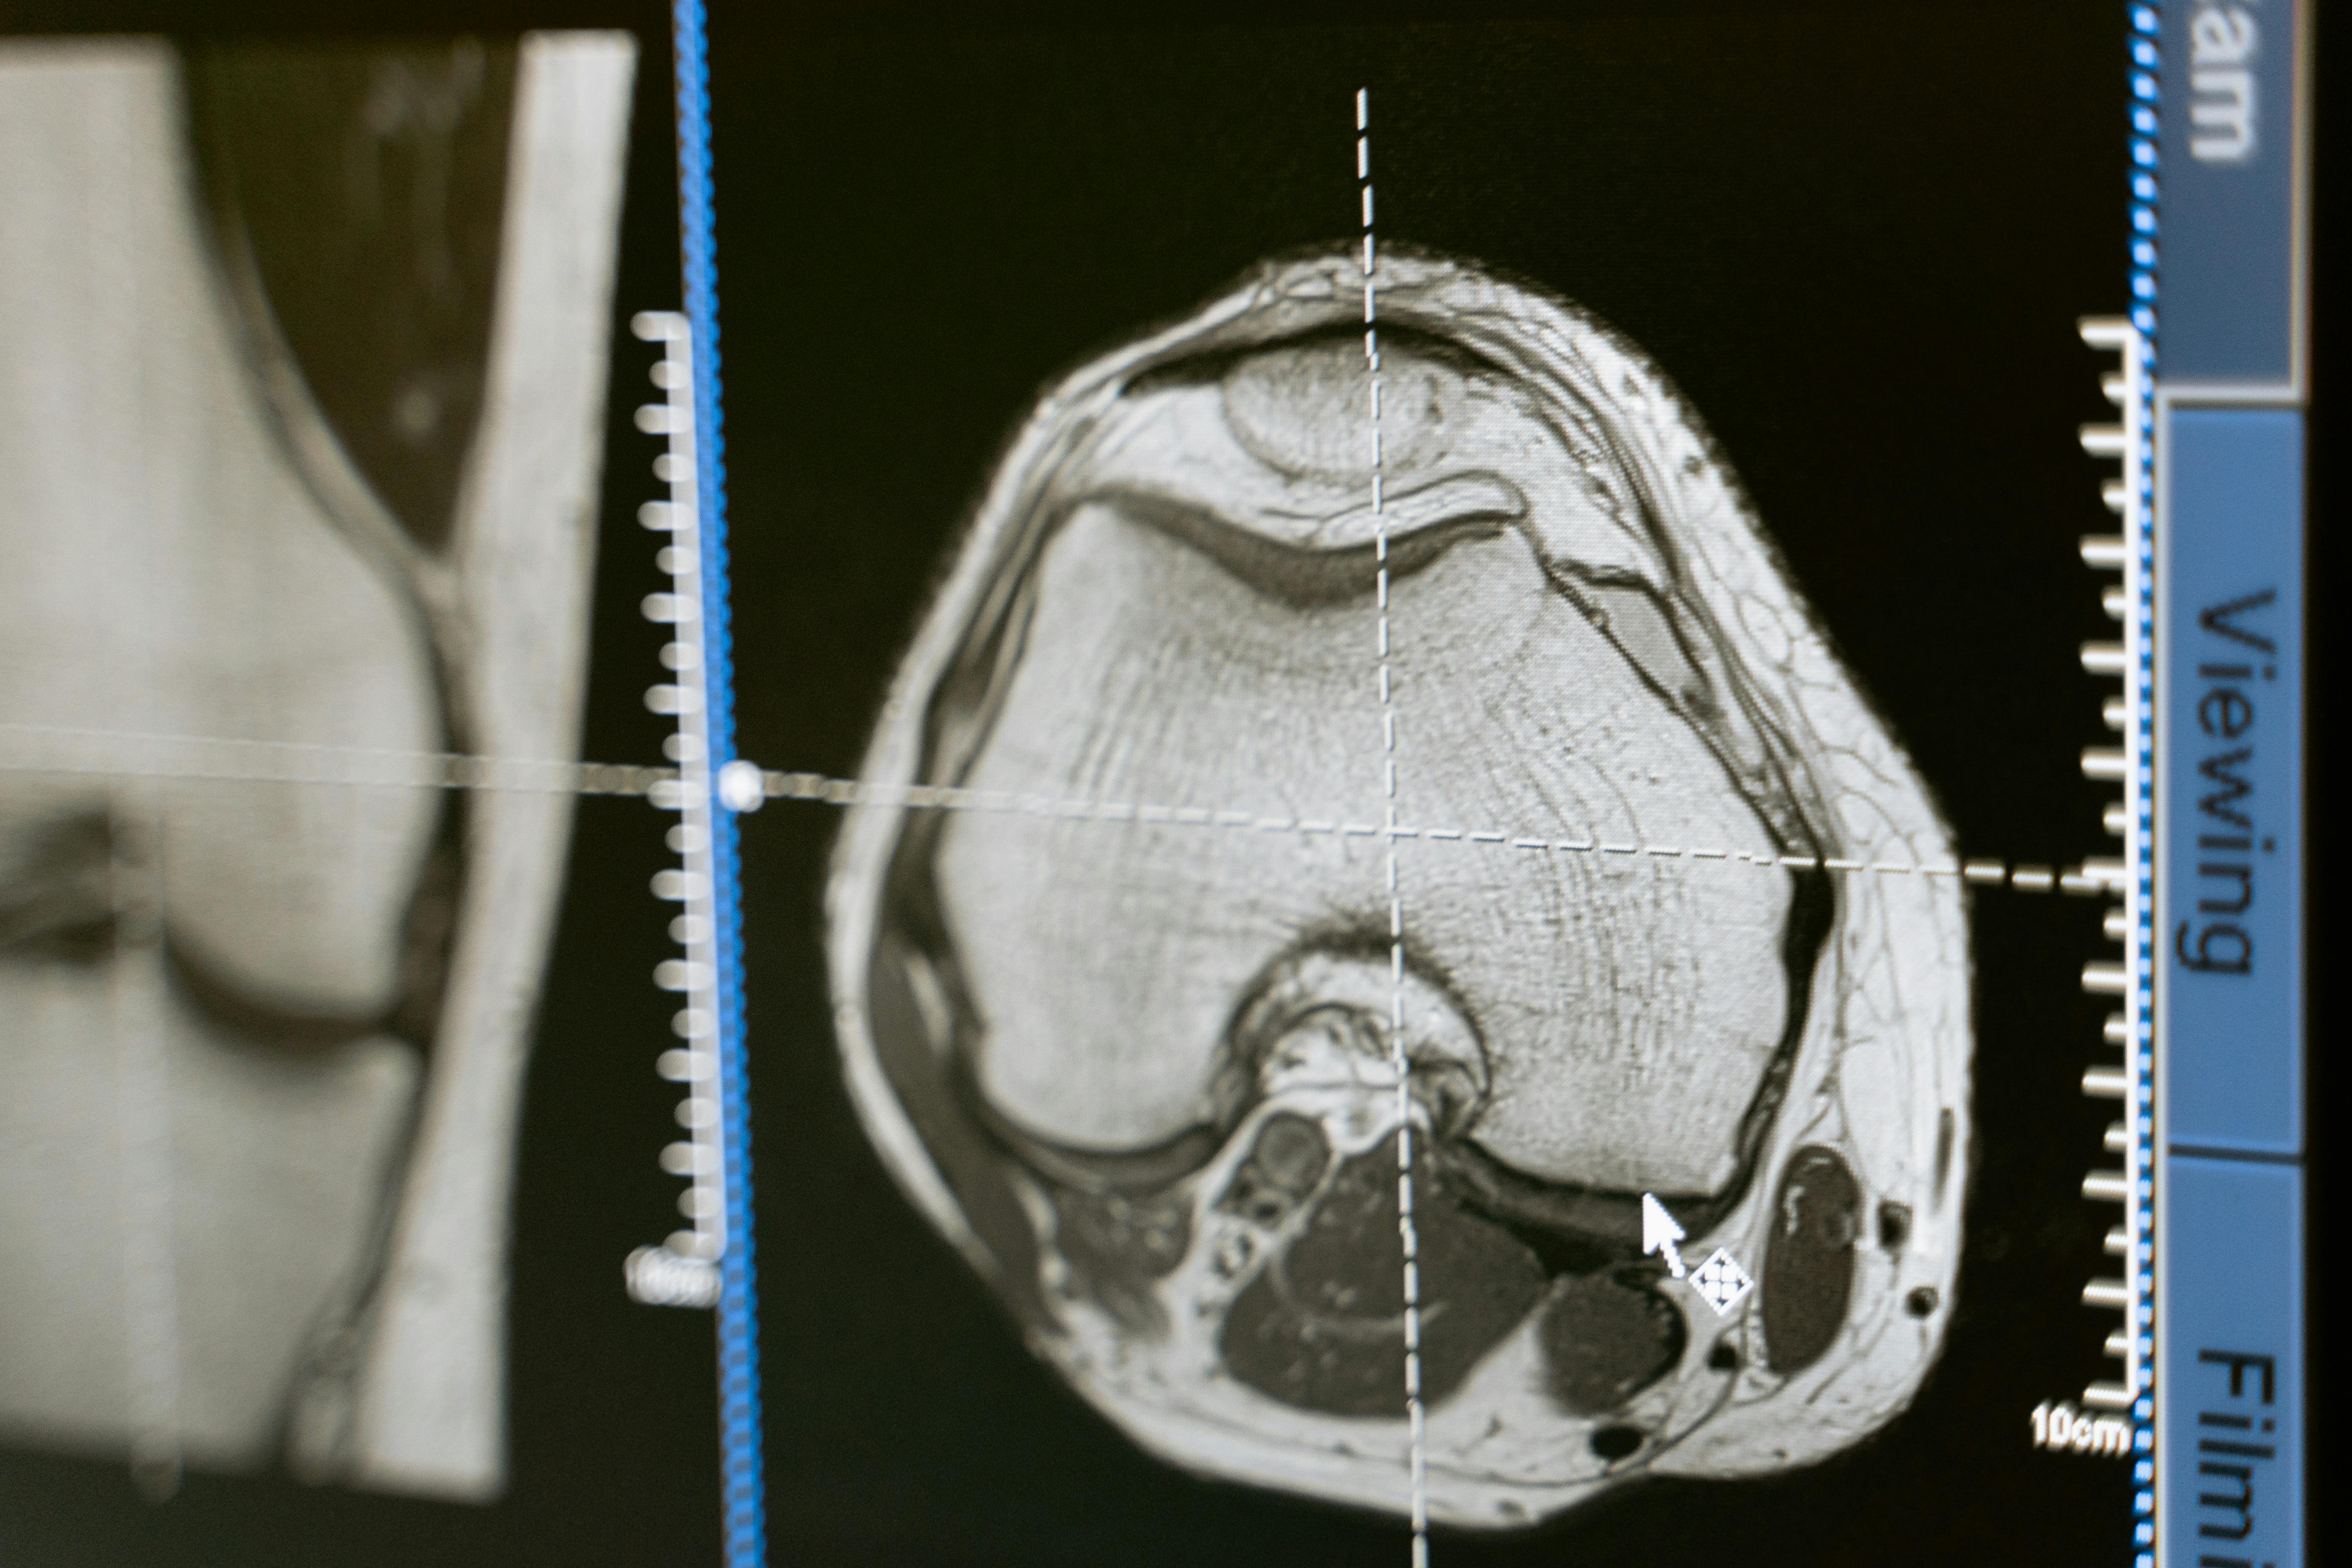

Advancements In Brain Imaging Technology At Brain Mapping Solutions Brain mapping solutions uses advanced mri and dti post processing software to visualize brain injuries in detail. their technology not only shows the injury location but also helps doctors understand the cognitive and behavioral impacts, making it easier to create personalized treatment plans. Brain mapping solutions inc is a cutting edge, patented neuro imaging software company committed to providing results and solutions for brain injury and neuro degenerative diseases. Brain mapping solutions inc is a cutting edge, patented neuro imaging software company committed to providing results and solutions for brain injury and neuro degenerative diseases. Brain mapping solutions offers advanced imaging technology that helps medical professionals link brain injuries to cognitive and behavioral deficits, providing clarity in diagnosis and treatment planning.